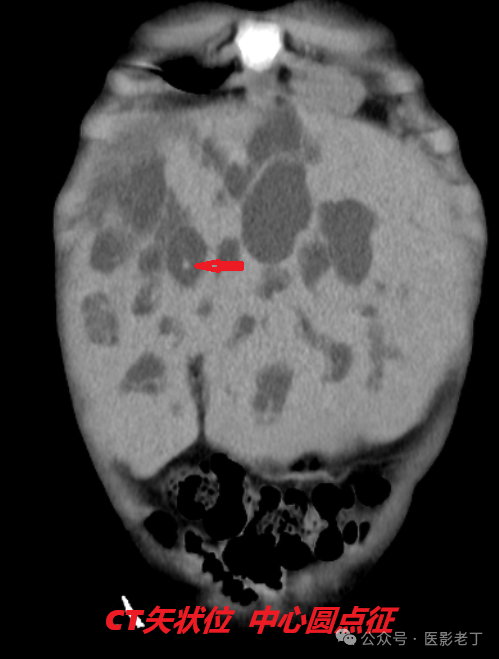

• 中心圆点征:增强CT上扩张的肝内胆管内可见小强化点(门静脉小分支);